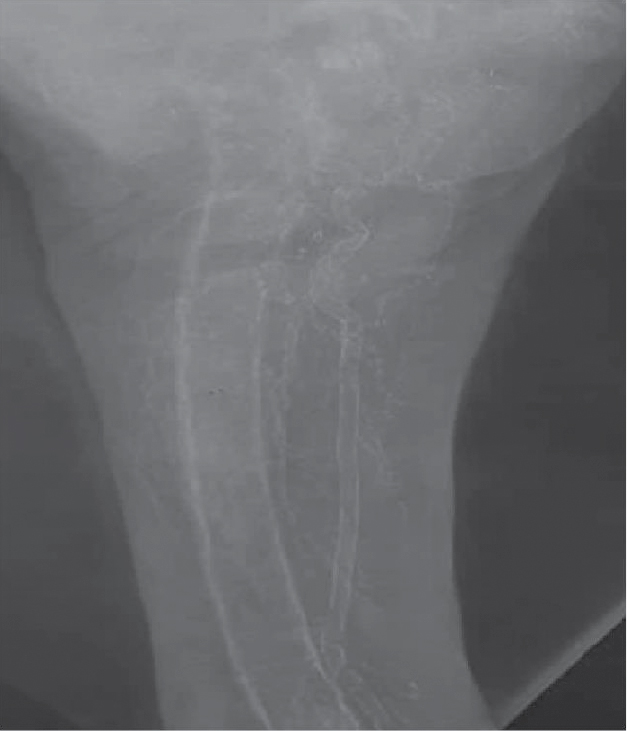

Although not clinically useful, the “gold standard” technique for the detection, assessment and quantification of vascular calcification is the histological examination of postmortem arterial specimens. Clinical detection is mostly by plain radiograph, which shows pipe stem (tram line) appearance in case of medial calcification (Fig. 1). CT scanning permits both the detection and quantification of the extent and severity of calcification. Vascular ultrasound can frequently show calcified plaques and calcified media. The use of plain lateral abdominal radiography or echocardiography to detect the presence or absence of vascular or valvular calcification, respectively has been endorsed by Kidney Disease: Improving Global Outcomes (KDIGO).11

Figure 1. X-ray thigh of a patient of CKD Stage 5D on maintenance hemodialysis with CKD-metabolic bone disease showing pipe stem (tram line) appearance suggestive of medial calcification of femoral artery.